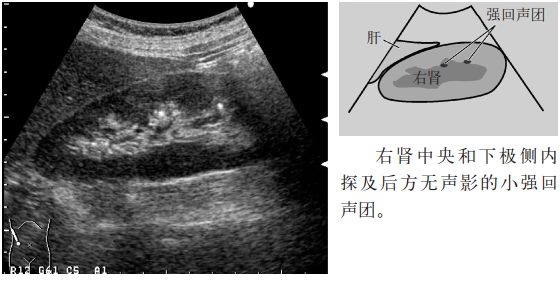

图3 肾结石

注意:小于5mm的肾结石几乎无声影,但是,超声入射角度微妙的变化可以显示点状高回声和声影。因此,平静呼吸时或改变经肋间扫查的位置,有时会出现声影,因此,不仅要在吸气时观察,还应在呼气时或改变经肋间扫查的位置时进行观察。